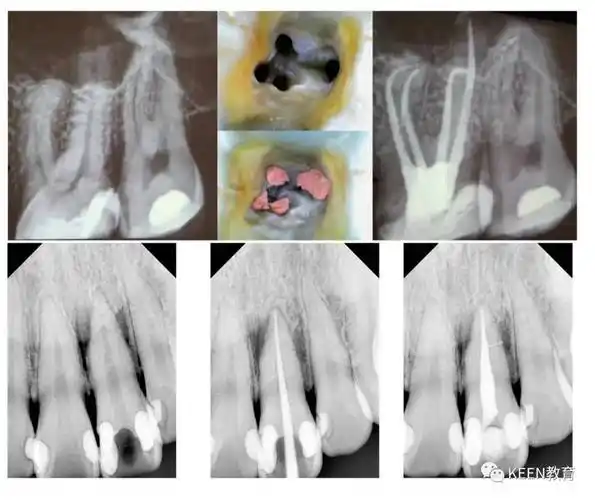

征文:新的征程之单颗牙修复--刘勇

未来之星——keen教育第八期《未来之星》训练营隆重